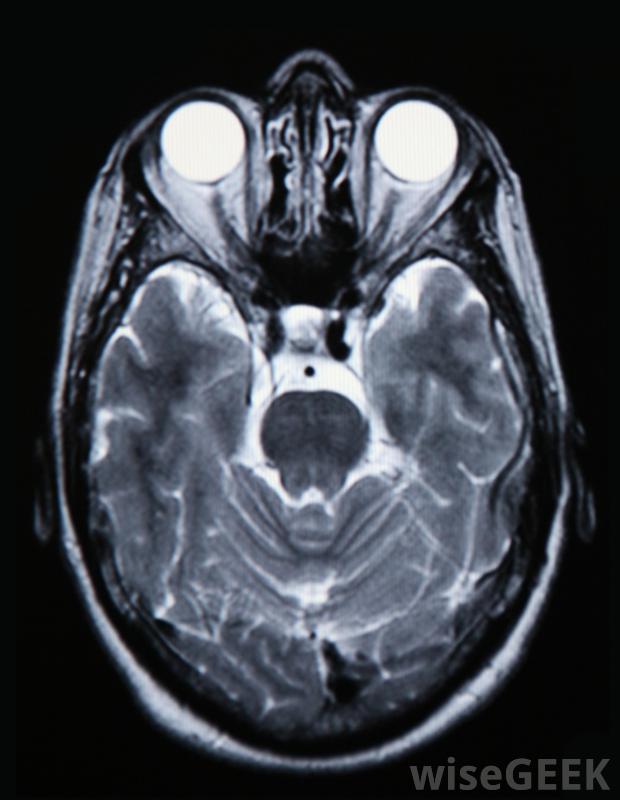

脑部扫描将显示肿瘤的位置,并帮助确定是否需要化疗使用化学疗法治疗脑瘤不像其他潜在的治疗方法那么普遍,原因有几个。大脑有一种保护机制,可以将化学物质和其他毒素排除在外。这在大多数情况下是有益的,但它也能阻止化疗药物进入脑瘤,非癌性肿瘤通常从不接受化疗,恶性肿瘤通常只有在进展后才使用药物治疗

大脑有一层保护膜,可以阻挡化学物质和毒素,从而阻止药物进入脑瘤为了确定使用化疗治疗脑瘤是否是一个好的选择,必须对大脑进行扫描,以确定肿瘤的位置和肿瘤的大小。可能要做一些测试来确定肿瘤是否是癌性的。如果不是,那么它们就很小,不会影响脑功能,医生们可能会采取观望的态度,仔细观察肿瘤的生长情况。如果发现有癌变,可以通过手术和放疗来切除或缩小肿瘤。